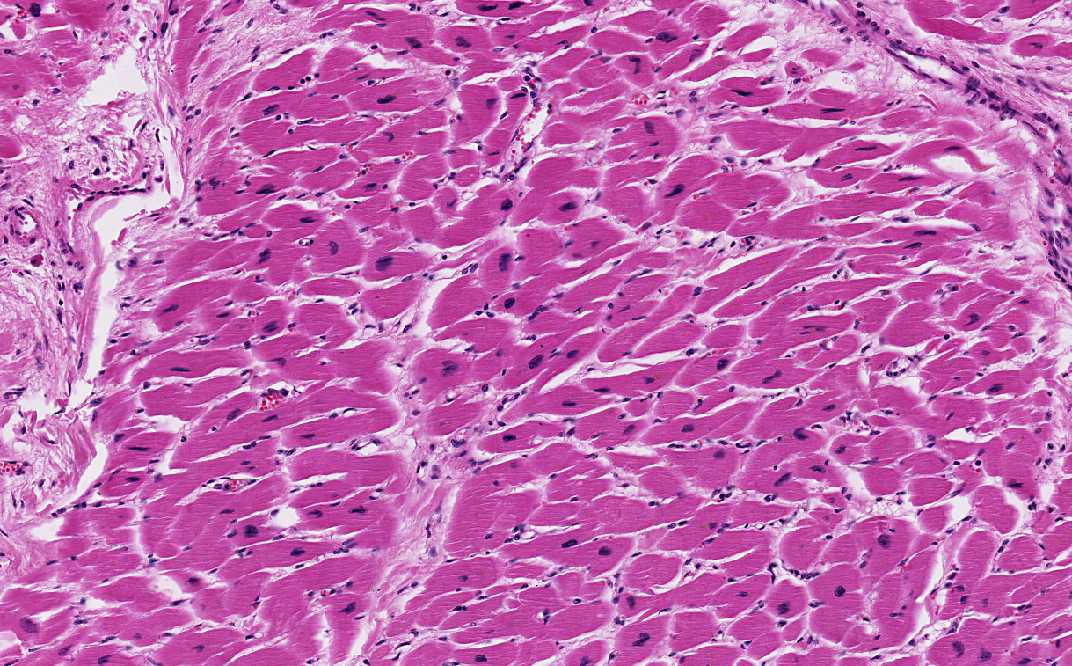

Heart- Area 1: The nuclei are hyperchromatic and are rectangular shape, the so-called "box-car nuclei".

• Heart: Patient with prolonged hypertension, the heart is typically grossly hypertrophic featured by concentric thickening of the left ventricular wall and increase in weight. Microscopically, here is diffuse hypetrophy of the cardiac muscle. The myocytes increases in width. The normal cardiac myocyte is about 10-15 microns in with but in the hypertrophyic myocytes, they can reach a width of 25 microns. The nuclei is also enlarged and hyperchromatic. They often adopt a rectangular shape and are termed "box-car nuclei". With the modern eyes, they do resemble minivans or SUVs! (Heart- Area 1)